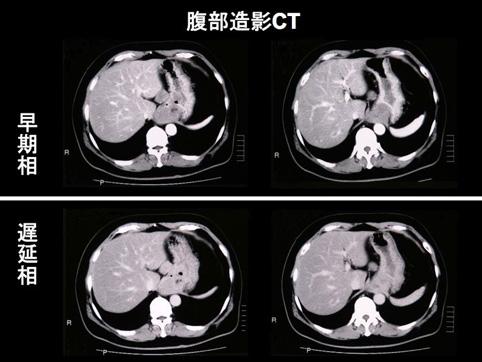

Criteria of Hist.ClassificationMalignant non-epithelilal tumors/Leiomyosarcoma (including GIST)

Technique, MethodCT

Macroscopic TypesType 2 Ulcerated type with clear margin/

Size40 -

Depth of Tumor Invasionsubserosa (subadventitia)